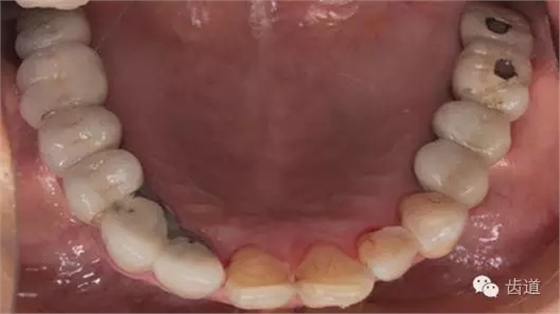

3、下頜牙合面觀

1、治療前